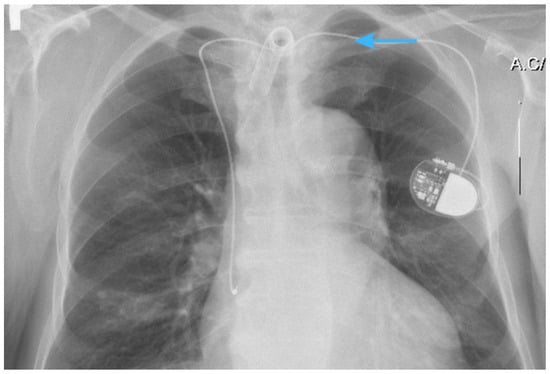

2.1. X-Ray Imaging